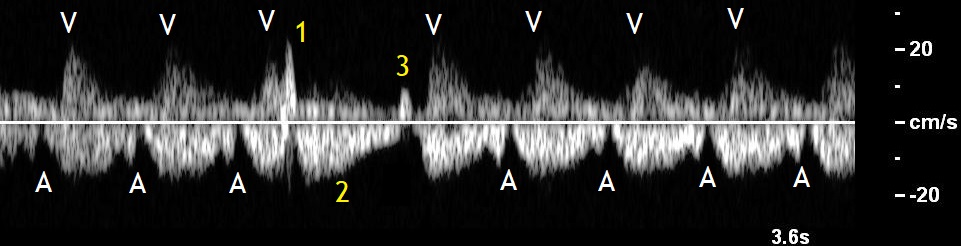

The premature atrial contractions follow a usually normal ventricular contraction and are seen in doppler ultrasound as deep a waves, because they hit on a closed atrioventricular valve. If they are conducted, they are followed by a ventricular contraction which appears to be smaller than usual, because of the smaller stroke volume. The next venous circle will be delayed because of the non-compensatory, post-extrasystolic pause and the ventricular contraction after this circle will be larger than usual. This phenomenon which is called post-extrasystolic potentiating is due to the intact Frank-Starling mechanism (Figure 3) (2).